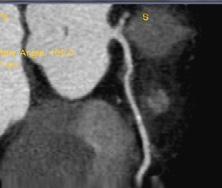

Figura 1. Pacient de 57ani cu simptomatologie acută sugestivă pentru AVC ischemic acut: CT -ul nativ nu a decelat elemente de semiologie sugestive pentru AVC ischemic acut (A), însă secvențele IRM au evidențiat o arie în hipersemnal FLAIR (B) și cu restricție de difuzie (C) localizată occipital paramedian dreapta, sugestivă pentru AVC ischemic acut (Spitalul Clinic de Urgență „Prof. N. Oblu“, Iași)

În contrast, imagistica prin rezonanță magnetică, în special secvențele de difuzie, oferă o sensibilitate superioară pentru detectarea precoce a infarctului ischemic,

fiind capabilă să identifice modificări la nivel celular la doar câteva minute după debutul simptomelor (Figura 1) (Mouridsen et al., 2020), (Nukovic et al., 2023). De asemenea, IRM este capabilă să ofere o evaluare superioară a integrității parenchimului cerebral, a viabilității țesutului și a extinderii leziunii ischemice, facilitând o caracterizare mai detaliată a AVC-ului ischemic (Cortés-Albornoz et al., 2025).